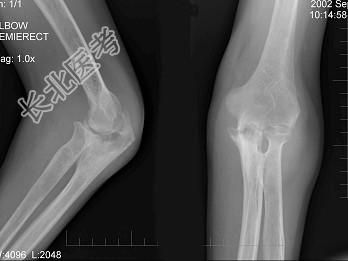

- 单项选择题男,61岁, 低烧,消廋, 胸片示有结核病灶,结合图像, 最可能诊断是 ( )

A、肘关节结核

B、肘关节退行性变

C、骨折

D、未见异常

E、类风湿关节炎